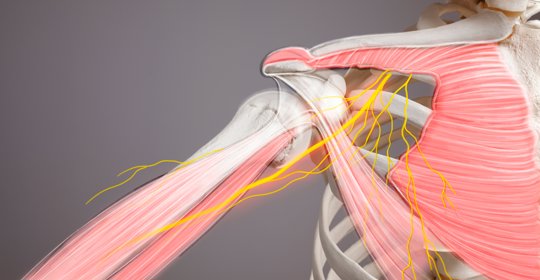

嬰兒腳氣:關注嬰幼兒支氣管炎並發症